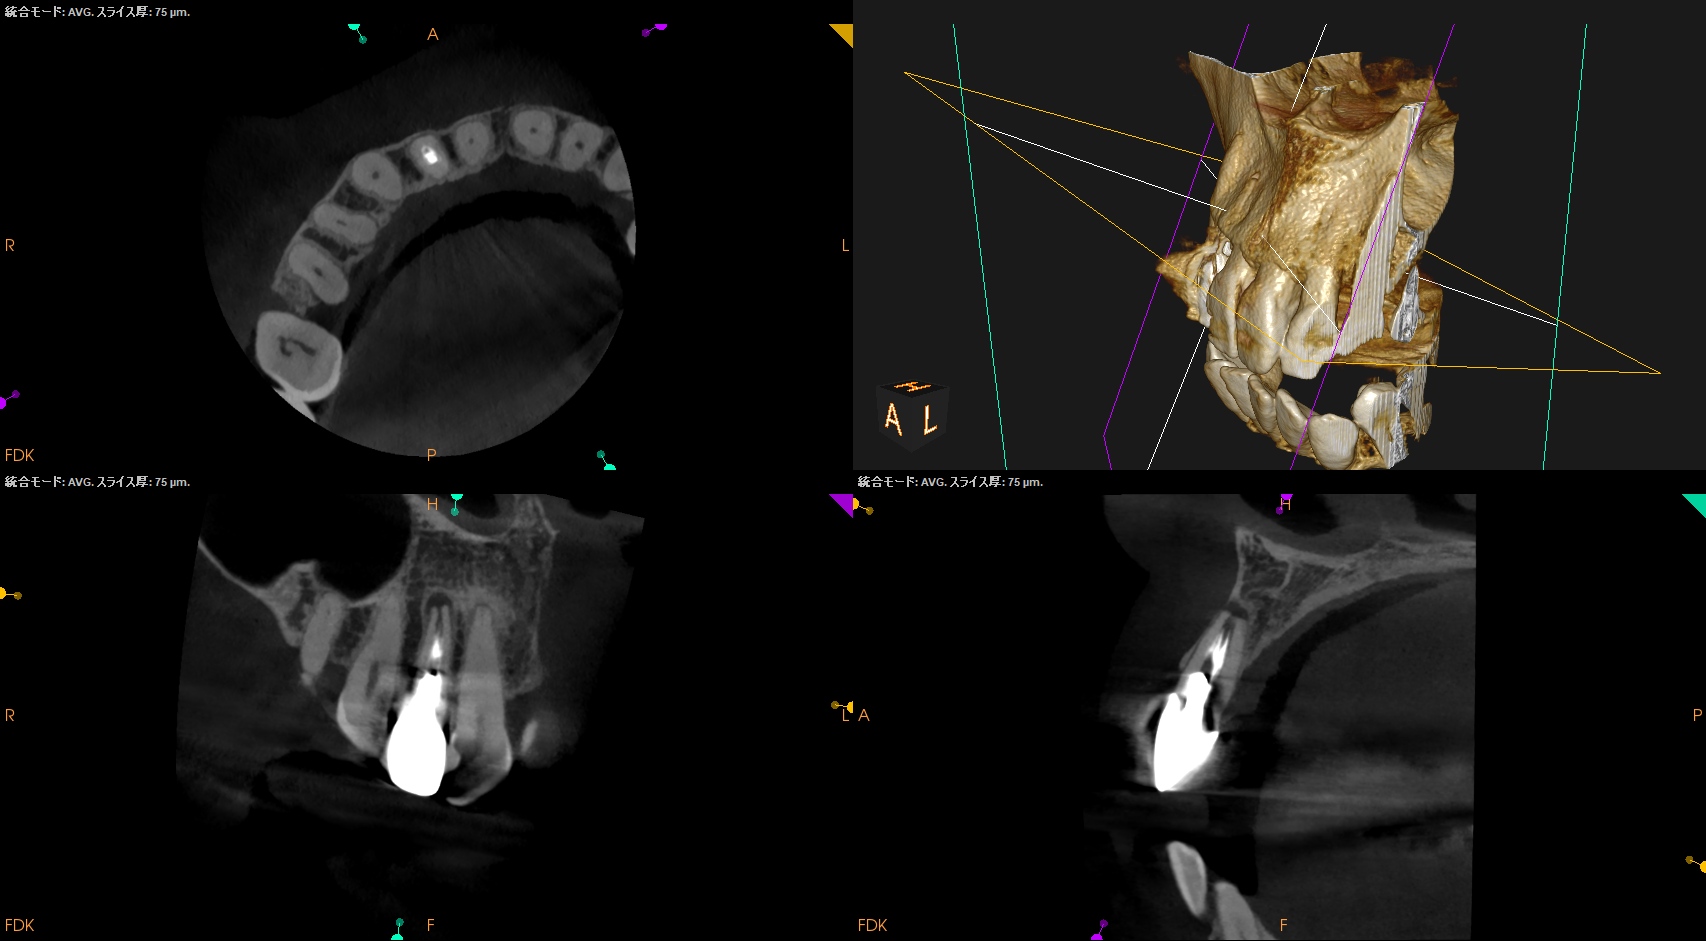

Pre-op Endo test(2025.1.24)

根尖が既に開いており、圧痛があったことから治療は再根管治療ではなく、歯根端切除術であるということがわかる。

クラウンのマージンより11.5mm下方に#7のApexはあり、そこを3mm切断するには頬舌的に4.4mmの幅があるということがわかる。

実にEasyなApicoectomyだ。

Pulp Dx: Previously treated

Periapical Dx: Asymptomatic apical periodontitis

Recommended Tx: Core build up w Fiber Post⇨Apicoectomy